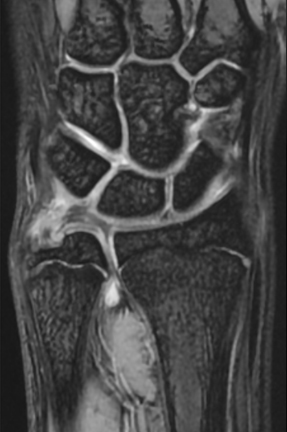

【MRI】

単純X線の他、MRI、手関節造影/CTを行います。単純X線では、TFCC自体は映りません。しかし、骨形態の評価、とくに突き上げ症候群の評価に有用であり、必須の検査の1つです。MRIではTFCCの損傷の有無を評価します。また、ECU腱鞘炎などその他の障害/疾患の有無を確認します。しかしながら、MRIではTFCCの詳細な評価が難しい場合があり、手関節造影/CTが必要となることがあります。手関節造影/CTでは、造影剤を橈骨手根関節内および遠位橈尺関節内に注入しTFCCの円盤部や末梢部、表層部、および小窩(Fovea)部などでの断裂形態を確認します。その他、手根骨間靱帯損傷や手関節尺側部の骨形態について評価します。